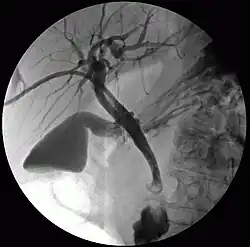

Colangiografia percutânea trans-hepática

Colangiografia percutânea transhepática (CPT) ou colangiografia percutânea trans-hepática é uma técnica radiológica usada para visualizar a anatomia do trato biliar. Um meio de contraste é injetado em um ducto biliar no fígado, após o qual os raios X são feitos. Permite o acesso à árvore biliar nos casos em que a colangiopancreatografia retrógrada endoscópica (CPRE) não tem êxito. Relatado inicialmente em 1937, o procedimento se tornou popular em 1952.[1][2]